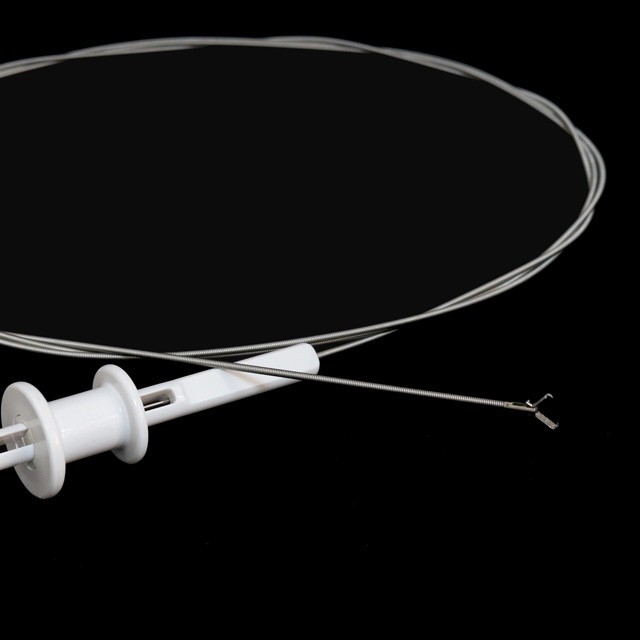

Prong tipe

|

Model |

Skede o . d . |

Werkende kanaal |

Werkslengte |

Funksies |

|

Fg -28 u-b3 |

2.3 |

Groter as of gelyk aan 2,8 |

2300 |

3- prong tipe |

|

Fg -28 u-b4 |

2.3 |

Groter as of gelyk aan 2,8 |

2300 |

4- prong tipe |

|

Fg -28 u-b5 |

2.3 |

Groter as of gelyk aan 2,8 |

2300 |

5- prong tipe |